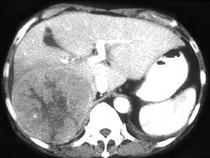

男,69岁,肝区疼痛,消瘦乏力三月余,CT检查如图,请作出最可能诊断()A.肝囊肿B.肝脓肿C.肝血管瘤D.肝转移瘤E.巨块型肝癌

问题 男,69岁,肝区疼痛,消瘦乏力三月余,CT检查如图,请作出最可能诊断()

选项 A.肝囊肿 B.肝脓肿 C.肝血管瘤 D.肝转移瘤 E.巨块型肝癌

答案 E